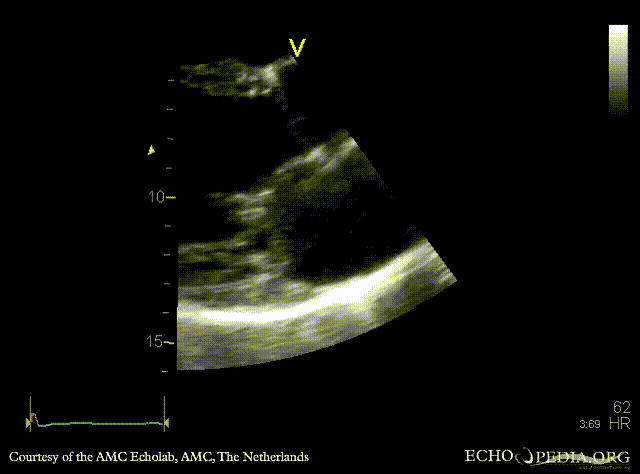

M-Mode through left ventricle, dilated LV